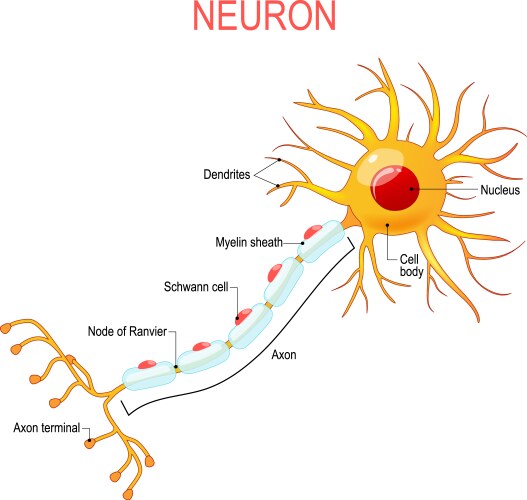

- Neuron